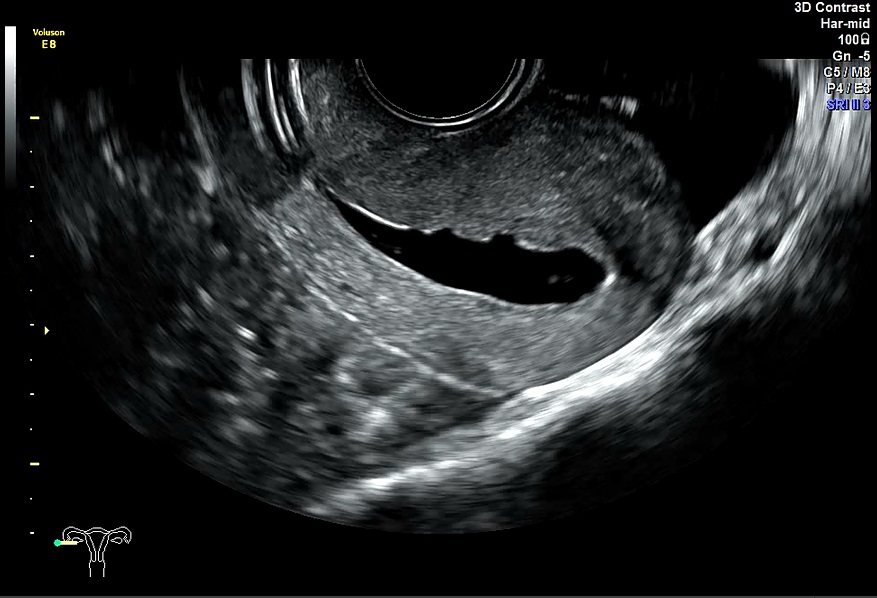

女性,30岁,继发性不孕1年余,有人流史。常规二维超声宫腔线清晰,中段内膜回声略不均匀。宫腔三维显示:宫腔呈倒三角形,宫角锐利,体部内膜可见小片偏高回声区。宫腔水造影显示:体部宫腔后壁数处不规则突起及条形低回声带。子宫输卵管实时三维超声造影显示:宫腔中部不规则充盈缺失。诊断:宫腔粘连,子宫内膜增生。